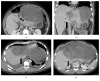

Undifferentiated embryonal sarcomas of the liver are extremely rare cases in adults. We report the case of a 30-year-old male who presented with early satiety and abdominal pain due to a massive tumor originating from the left liver and occupying the entire epigastrium. The patient underwent bland embolization in an attempt to decrease the size of the tumor. He then underwent a formal left hepatectomy with resection of liver segments 2, 3, and 4. Extrahepatic inflow control of the portal vein and hepatic artery was performed prior to parenchymal transection. No Pringle maneuver was required. Pathology analysis showed a 45 cm tumor consistent with an undifferentiated embryonal sarcoma and negative microscopic margins. The epidemiology, treatment, and prognosis of this unusual cancer presentation are reviewed.